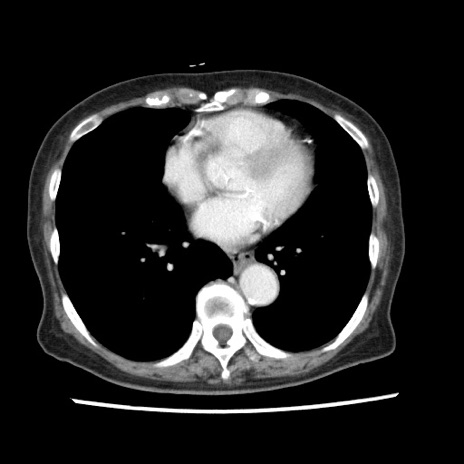

症例1(横断像)

【症例】80歳代女性

【主訴】腹痛

【現病歴】8時間前から腹痛あり来院。

【既往歴】糖尿病、脂質異常症、子宮体癌にて子宮全摘術

【身体所見】意識清明・会話良好だが腹痛で苦悶様、全腹部にわたって反跳痛と圧痛あり

【データ】WBC 13600、CRP 0.14、LDH 224、CK 90